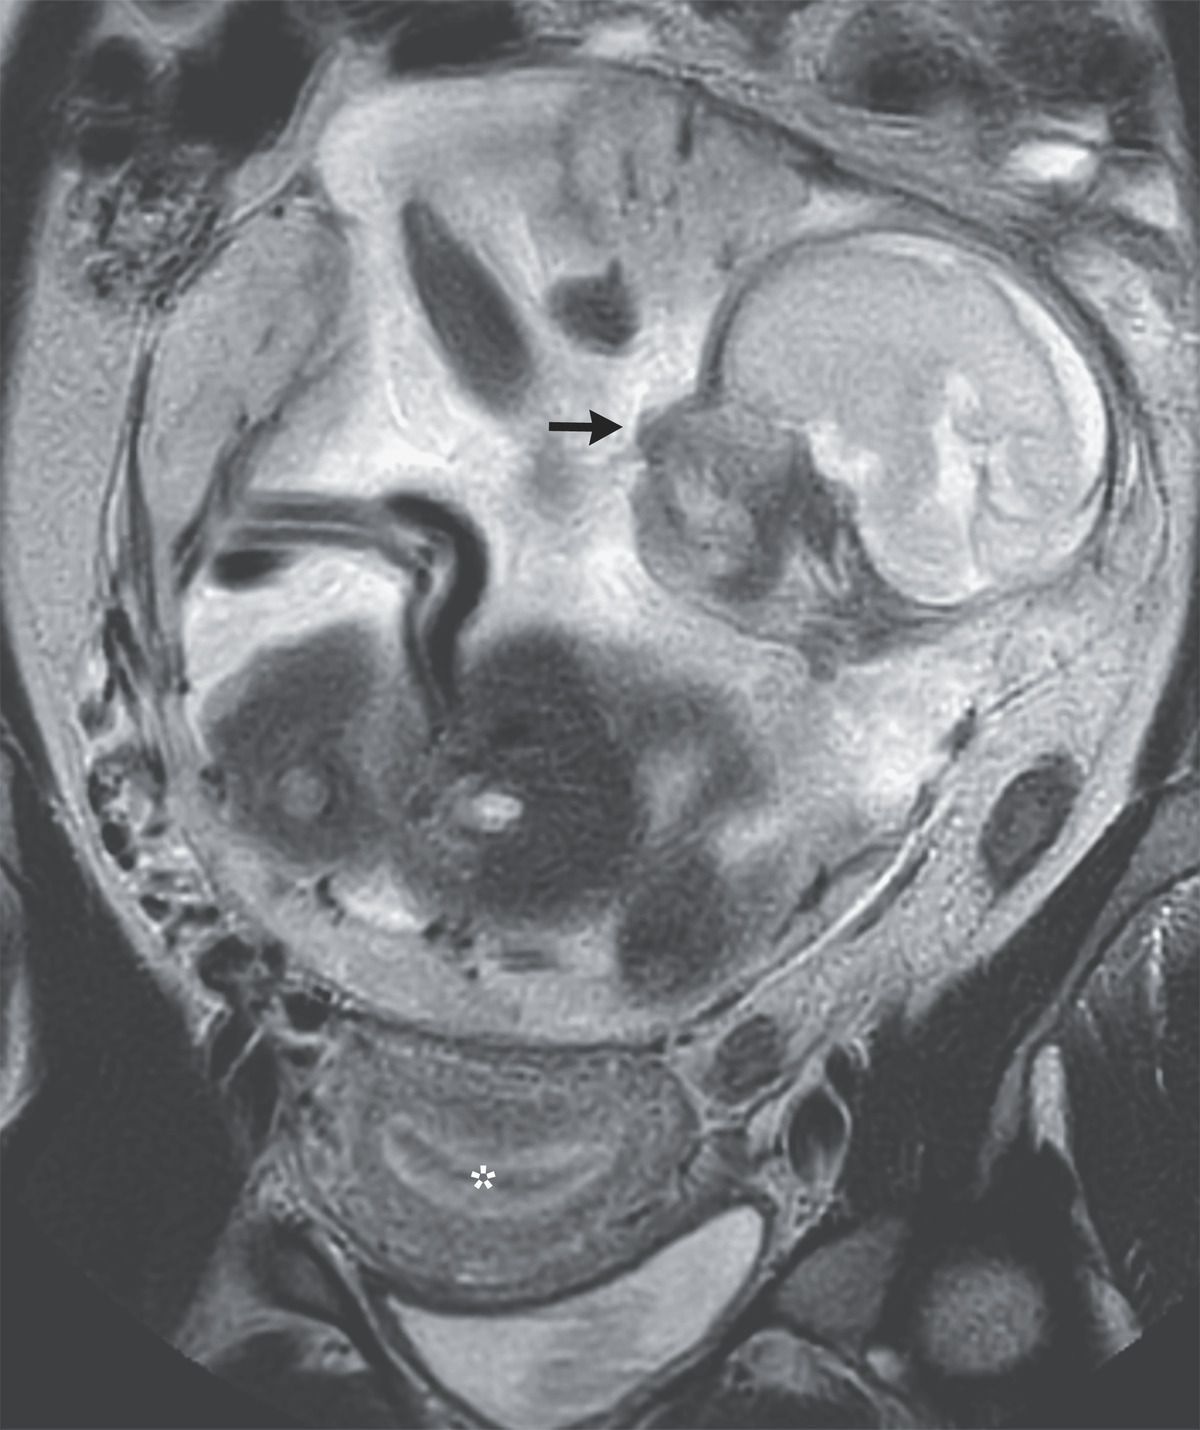

A 37-year-old woman who lived on a remote island presented to the emergency department with a 10-day history of abdominal pain. She had a history of two vaginal deliveries at full term, one miscarriage, and no sexually transmitted infections or previous surgeries. The physical examination was notable for a gravid abdomen. Ultrasonography revealed a thickened endometrium, empty uterus, and abdominal pregnancy at 23 weeks’ gestation. Magnetic resonance imaging of the abdomen subsequently showed a nongravid uterus (asterisk), a normally formed intraabdominal fetus (arrow), and a placenta that attached to the peritoneum above the sacral promontory. A diagnosis of abdominal pregnancy — a rare type of ectopic pregnancy — was made. Owing to the high risk of maternal hemorrhage and fetal demise, the patient was transferred to a tertiary care hospital. At 29 weeks’ gestation, a laparotomy with infant delivery, placental arterial embolization, and partial removal of the placenta was performed. The baby, who had Apgar scores of 2 and 6 at 1 minute and 5 minutes, respectively, was admitted to the neonatal intensive care unit. On postoperative day 12, the remaining placenta was surgically removed. The mother and the baby were discharged home 25 days and 2 months, respectively, after the birth. The mother, who had declined contraception post partum, was lost to follow-up.